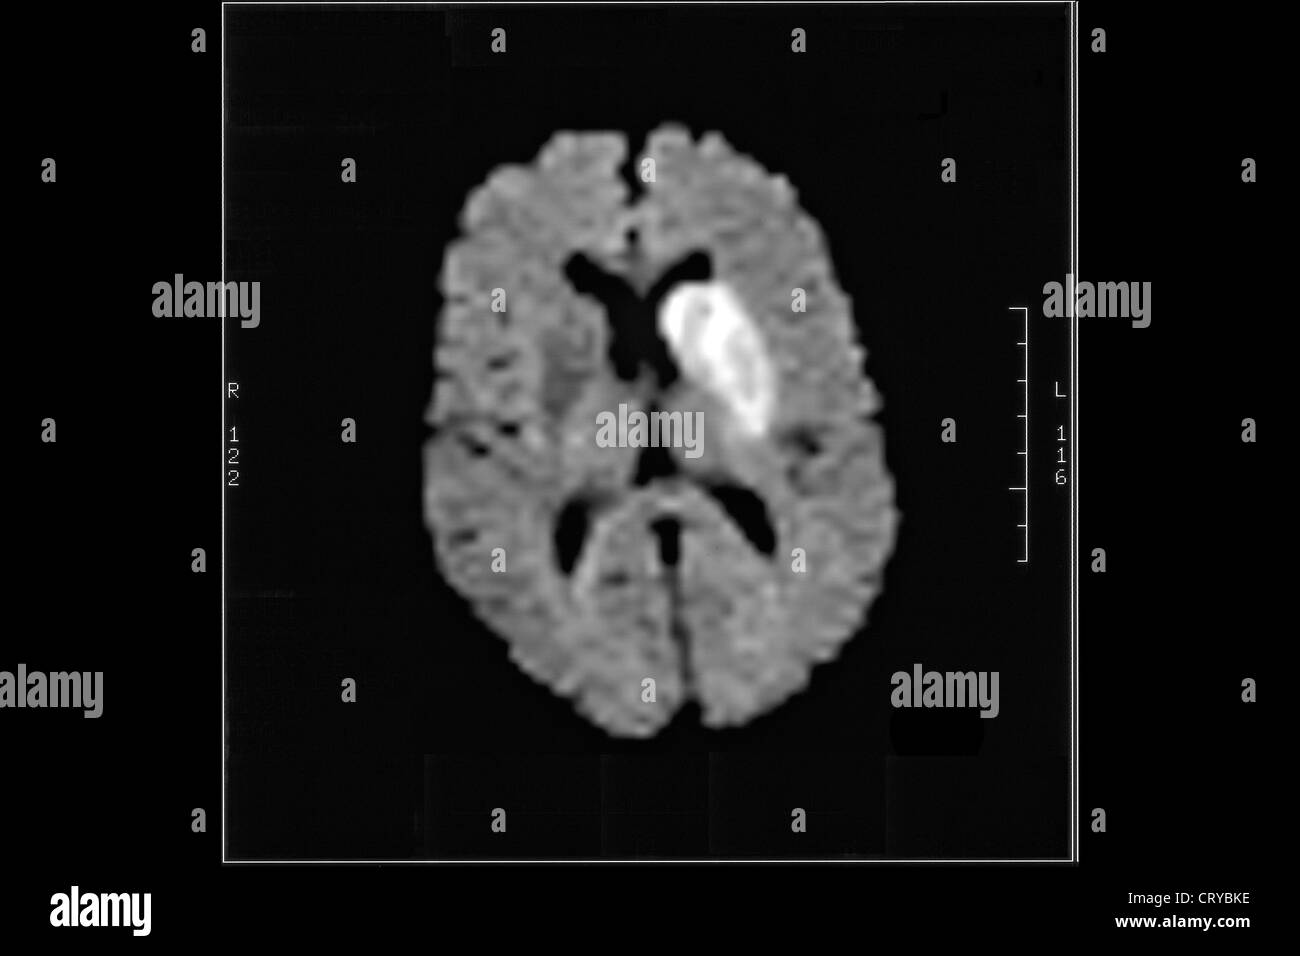

From www.alamy.com

CEREBROVASCULAR DISEASE, MRI Stock Photo, Royalty Free Image 49159698 What Are Cerebrovascular Diseases This decreases the amount of. Cerebrovascular disease is a group of conditions that includes stroke, transient ischemic attack, aneurysms, and blocked arteries. This article explains the symptoms of these conditions,. This alteration of blood flow can sometimes impair the brain’s. Cerebrovascular disease is a term for conditions that affect the blood vessels that supply blood to your brain. Learn about. What Are Cerebrovascular Diseases.